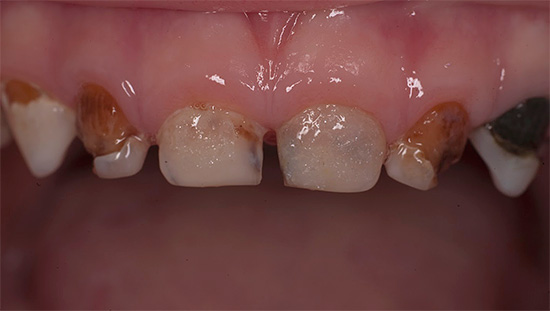

La seguente foto mostra un tipico esempio di carie di bottiglie:

La carie in bottiglia è una malattia dei bambini di età compresa tra 2 e 3-4 anni. Il nome piuttosto originale di questa malattia è dovuto a una delle sue cause: la carie in bottiglia nei bambini si sviluppa a causa dell'abitudine di bere latte o miscele di latte da una bottiglia prima di coricarsi o nel cuore della notte, dopo di che una grande quantità di cibo rimane in bocca per tutta la notte, che sono le principali fattore cariogeno.